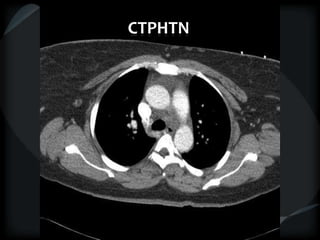

Mosaic CT Patterns

 Ground glass – inflammation/ fibrosis

 airway obstruction (best seen on expiration)

• COPD

• small airway disease

 Vascular obstruction

• chronic thrombotic pulmonary hypertension

• sickle cell disease

• vasculitis

Vascular obstruction

CTPHTN

ground glass